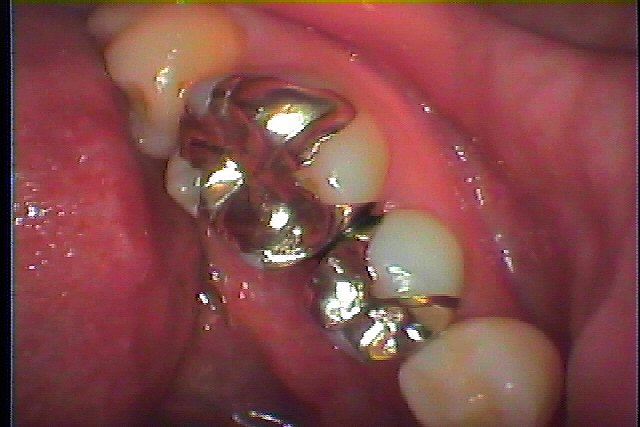

ブログ一覧|広島市安佐南区の歯科医院 ブログ一覧 トップ ブログ一覧 お知らせ スタッフブログ ブログ一覧 お知らせ 2018/09/04 右上6番の銀歯のやり変え お知らせ 2018/09/04 左下6番 急な痛みにて お知らせ 2018/09/04 左下5,6番の銀歯のやり変え お知らせ 2018/09/03 右下6番 虫歯治療 お知らせ 2018/09/03 左下7番虫歯治療 お知らせ 2018/09/03 右上の6番クラウン 根の治療からのセラミッククラウン お知らせ 2018/09/03 左下の7版銀歯を白く綺麗にしたい お知らせ 2018/09/03 虫歯治療 右上6番 << 1 2 3 4 5 … 476 477 478 479 480 … 870 871 872 873 874 >> Web診療予約 初めての方へ 選ばれ続ける理由 院内設備について 歯が痛いしみる一般歯科 歯がぐらぐらする歯周病 健康な歯を保ちたい予防歯科 子供の虫歯予防をしたい小児歯科 銀歯をセラミックに審美歯科 白い歯を目指しませんか?ホワイトニング 矯正専門医がいるので安心矯正歯科 抜けた歯を補いたいインプラント・入れ歯 医院案内 スタッフ紹介 メリィハウス歯科クリニックオフィシャルホームページ ラベンダー歯科クリニックオフィシャルホームページ お知らせ・ブログ ホーム 診療科目 一般歯科 歯周病治療 予防治療 小児歯科 審美治療 ホワイトニング 矯正歯科 入れ歯・インプラント マウスピース矯正 初めての方へ 院長・スタッフ 設備紹介 医院案内・アクセス メニューを閉じる